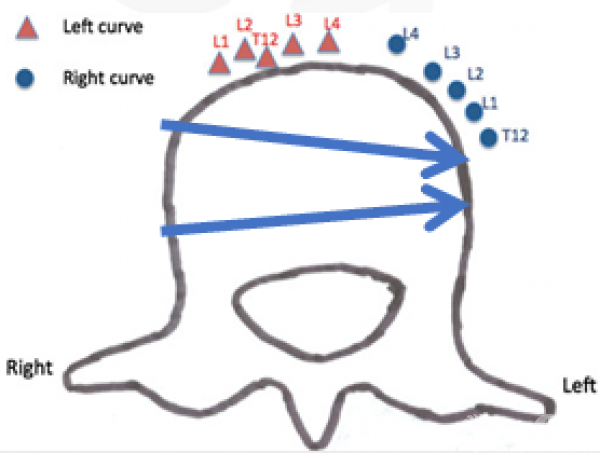

不同侧凸方向的Lenke 5C型AIS前路矫形疗效比较

邱勇教授团队[8]为了比较不同侧凸方向的Lenke 5C型脊柱侧凸前路矫形内固定的手术疗效。按照侧凸方向分为左侧凸组(L组,n=38)和右侧凸组(R组,n=14)。两组术前主弯Cobb角、主弯累及节段及代偿胸弯Cobb角均无显著差异(P>0.05)。L组、R组平均随访时间分别为3.1±0.9年(2~4年)、2.7±0.8年(2~3年)。两组均无血管损伤及神经并发症,无1例发生内固定失败。L组术后2例患者发生远端Adding-on,1例患者发生近端交界性后凸;R组1例出现近端Adding-on。

研究中左侧凸较右侧凸的手术时间短、出血量少,可能与侧凸方向导致的临床解剖差异对手术操作的影响有关。也因为解剖差异,在右侧凸患者中,椎体置钉时主动脉损伤的风险更高。

Jun Qiao等人[9]研究发现由于脊柱两侧的大血管分布存在差异,左侧的主动脉壁厚弹性较好,不易致钝性损伤;右侧的下腔静脉壁薄弹性较差,容易损伤。

同时他们通过CT观察发现左与右侧凸的胸腰弯/腰弯AIS患者主动脉与脊椎的相对位置存在差异,由于脊椎向凸侧旋转,在左侧凸患者中,主动脉从正常时的椎体左侧旋转至椎体前方偏右的位置;而在右侧凸中,主动脉向椎体左后方旋转,这预示在右侧凸患者中,椎体置钉时主动脉损伤的风险更高。

图9.左侧凸椎体钉与主动脉位置关系

图10.右侧凸椎体钉与主动脉位置关系